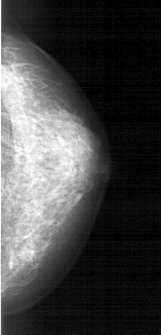

A_1609_1.LEFT_MLO

LEFT_MLO LINES 5191 PIXELS_PER_LINE 2056 BITS_PER_PIXEL 12 RESOLUTION 43.5 OVERLAY